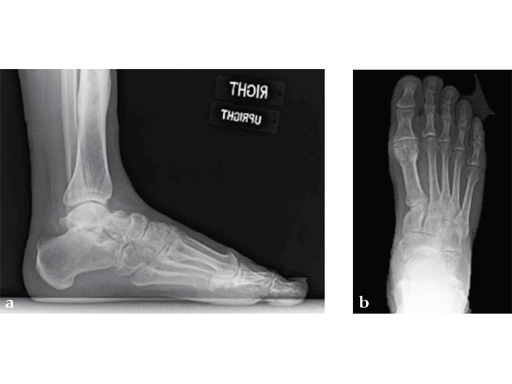

Case 2: First MTP fusion plate

A 38-year-old man presented for opinion after two attempts to fuse the big toe MTP joint. The AP view is significant for luscency at the joint line. The lateral view is notable for loosening of the hardware and malposition because of the dorsiflexion built in to the precontoured implant. Revision was planned using a 0 variable angle locking/compression hallux MTP plate.

Case provided by Michael Castro, Scottsdale, Arizona

At 10 weeks postoperatively (see Fig. 2ab) the patient had no pain with weight bearing. The lateral view demonstrates improved position of the toe using a 0angle plate.